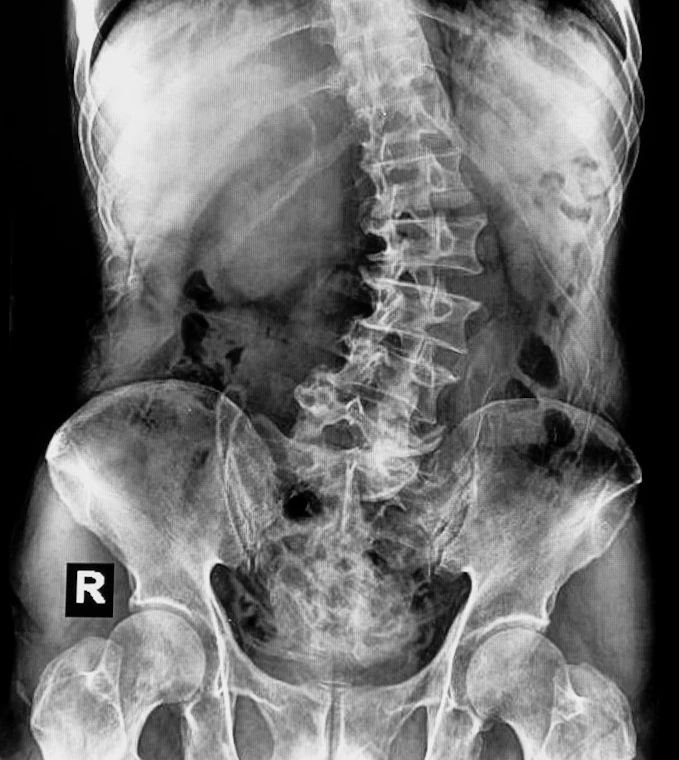

Scoliosis is an abnormal curvature of the spine. An S-shape is generally called scoliosis, a hump is called kyphosis, and a swayback is called hyperlordosis. Dr. Stan G. Langford III offers chiropractic care for scoliosis treatment for mild to moderate cases at his Chula Vista, CA, practice.

Scoliosis runs in families, but doctors often don’t know the cause. More females than males have severe scoliosis. Adult scoliosis may be a worsening of a condition that began in childhood but wasn’t diagnosed or treated. In other cases, scoliosis may result from a degenerative joint condition in the spine, like osteoporosis where the bones soften and allow the vertebrae to bend.

Scoliosis symptoms can often be viewed by looking at your child from behind. One hip or shoulder may look higher, one shoulder blade may stick out more than the other, or the head may not look centered over the body. In many cases, scoliosis does not cause pain until it progresses to a more severe case. Early detection and scoliosis treatment is key to avoiding painful scoliosis that interferes with a child’s play or sporting activities.

In order to correct scoliosis, the normal cervical and lumbar curves must first be re-established. Which is why bracing and surgery ultimately fail in so many cases, as these approaches do not address the full spine. Once accomplished, adverse tension on the spinal cord is reduced and allows for correction in the lateral dimension.